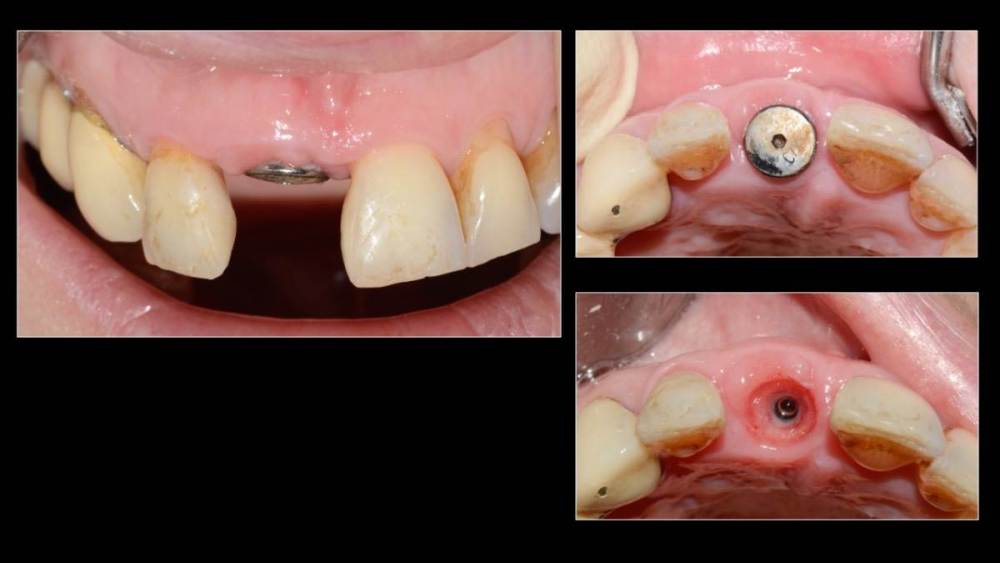

Владмир Опубликовано 20 марта, 2023 Автор Поделиться Опубликовано 20 марта, 2023 Здравствуйте коллеги. Работе 10 лет. Фото начальных этапов добавил 7 1 2 Ссылка на комментарий